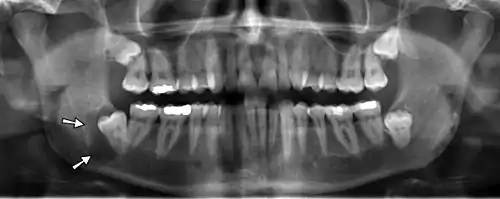

X-ray64A

Arrows point to two vertical white lines which is how calcifications in the first part (proximal component) of the internal carotid artery appear on panoramic radiographs.

X-ray64B

A line drawing depicting a panoramic radiograph with an ovoid atheroma in the bifurcation region of the common carotid artery (CCA) as it bifurcates (divides) in the neck into the internal carotid artery (ICA) which supplies blood to the brain and the external carotid artery (ECA) which supplies blood to the face and mouth.

Panoramic radiographs have the capability to demonstrate a portion of the neck and display atheromas (calcifications in the carotid artery) which are an indication of both local and generalized (systemic) atherosclerosis. Atherosclerosis of the coronary arteries leading to myocardial infarction (heart attack), and atherosclerosis of the carotid artery leading to stroke are the number one and number three most common causes of death in the United States.[6]